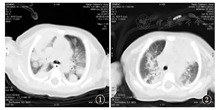

患儿,男,14 d,因发热2 d入院,入院前2 d无明显诱因出现发热,体温最高达38.9 ℃,予物理降温后可降至正常,间隔数小时后复升,不伴抽搐、吐泻等表现,精神反应及吃奶可,2 d未排大便,尿量不少。出生6 d因未排大便,有喂蜂蜜水病史。生活环境较潮湿。入院查体精神反应欠佳,呼吸平,无发绀,面部可见散在脓疱疹,前囟平软,双肺可闻及中细湿啰音,心音有力,律齐,腹软不胀,脐轮红,可见少许脓性渗出,四肢活动自如,末梢循环可。血白细胞25.4×109/L,中性粒细胞比为0.677,C反应蛋白(CRP)48.6 mg/L,入院后诊断为新生儿肺炎,根据血常规不除外新生儿脓毒症,先后予注射用拉氧头孢钠及头孢吡肟抗感染治疗,体温仍不稳定,后换为美罗培南治疗14 d,期间血培养示表皮葡萄球菌感染,加用利奈唑胺治疗11 d,经上述治疗患儿仍有发热,虽查血1,3–β–D葡聚糖抗原(G试验)检测(–),仍不除外真菌感染的可能,加用氟康唑胶囊治疗,住院16 d,尿培养示白假丝酵母菌感染,查血清半乳甘露聚糖抗原(GM)试验5.127(正常值为0~0.5),支持侵袭性曲霉菌感染。胸片示新生儿肺炎,肺部CT示双肺可见多发散在团状及结节状高密度影,诊断为肺曲霉菌病(图1)。换用伏立康唑12 mg/(kg·d ),每12 h 1次,治疗1 d后改为8 mg/(kg·d ),每12 h 1次,继续抗真菌治疗,静脉用药12 d后改为口服伏立康唑片序贯治疗(剂量同前),患儿因病情好转出院门诊继续治疗。出院2个月余,患儿体温正常,咳嗽不明显,肺部啰音基本吸收,复查肺CT示病变部位较前吸收和钙化(图2)。住院期间及出院3个月2次结核菌素试验试验(–),目前仍口服伏立康唑治疗。